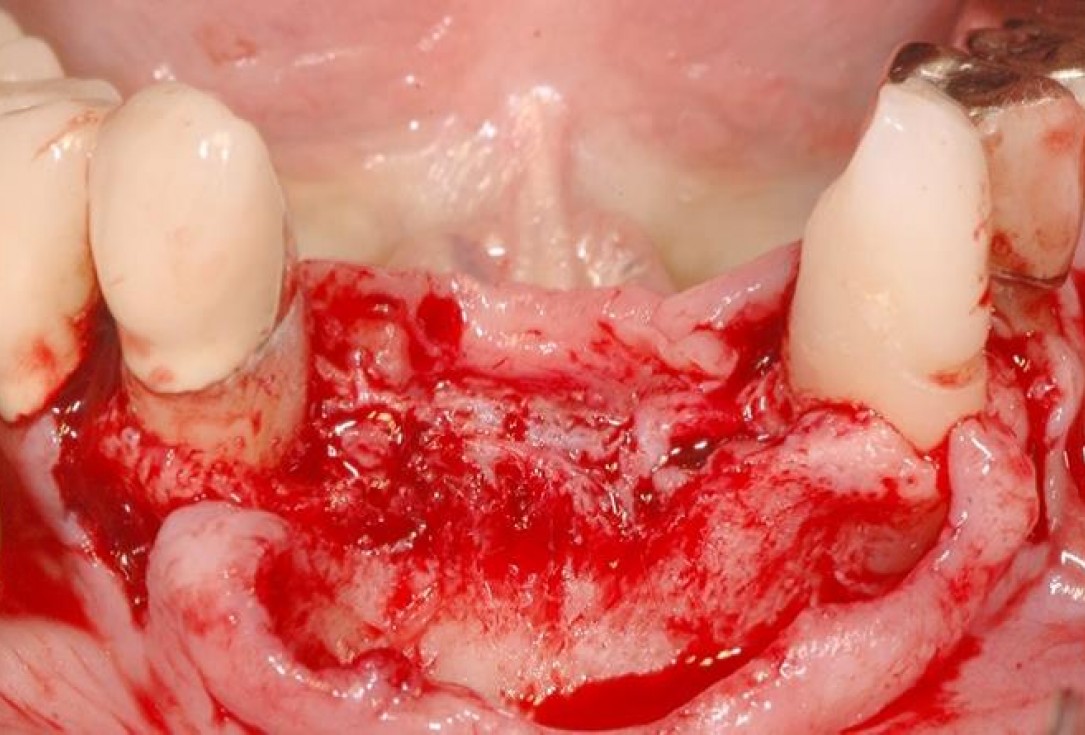

3/15 - Defect dimensions visible after full thickness flap preparationSoft tissue augmentation and GBR with mucoderm® and maxresorb® - Dr. S. Scherg